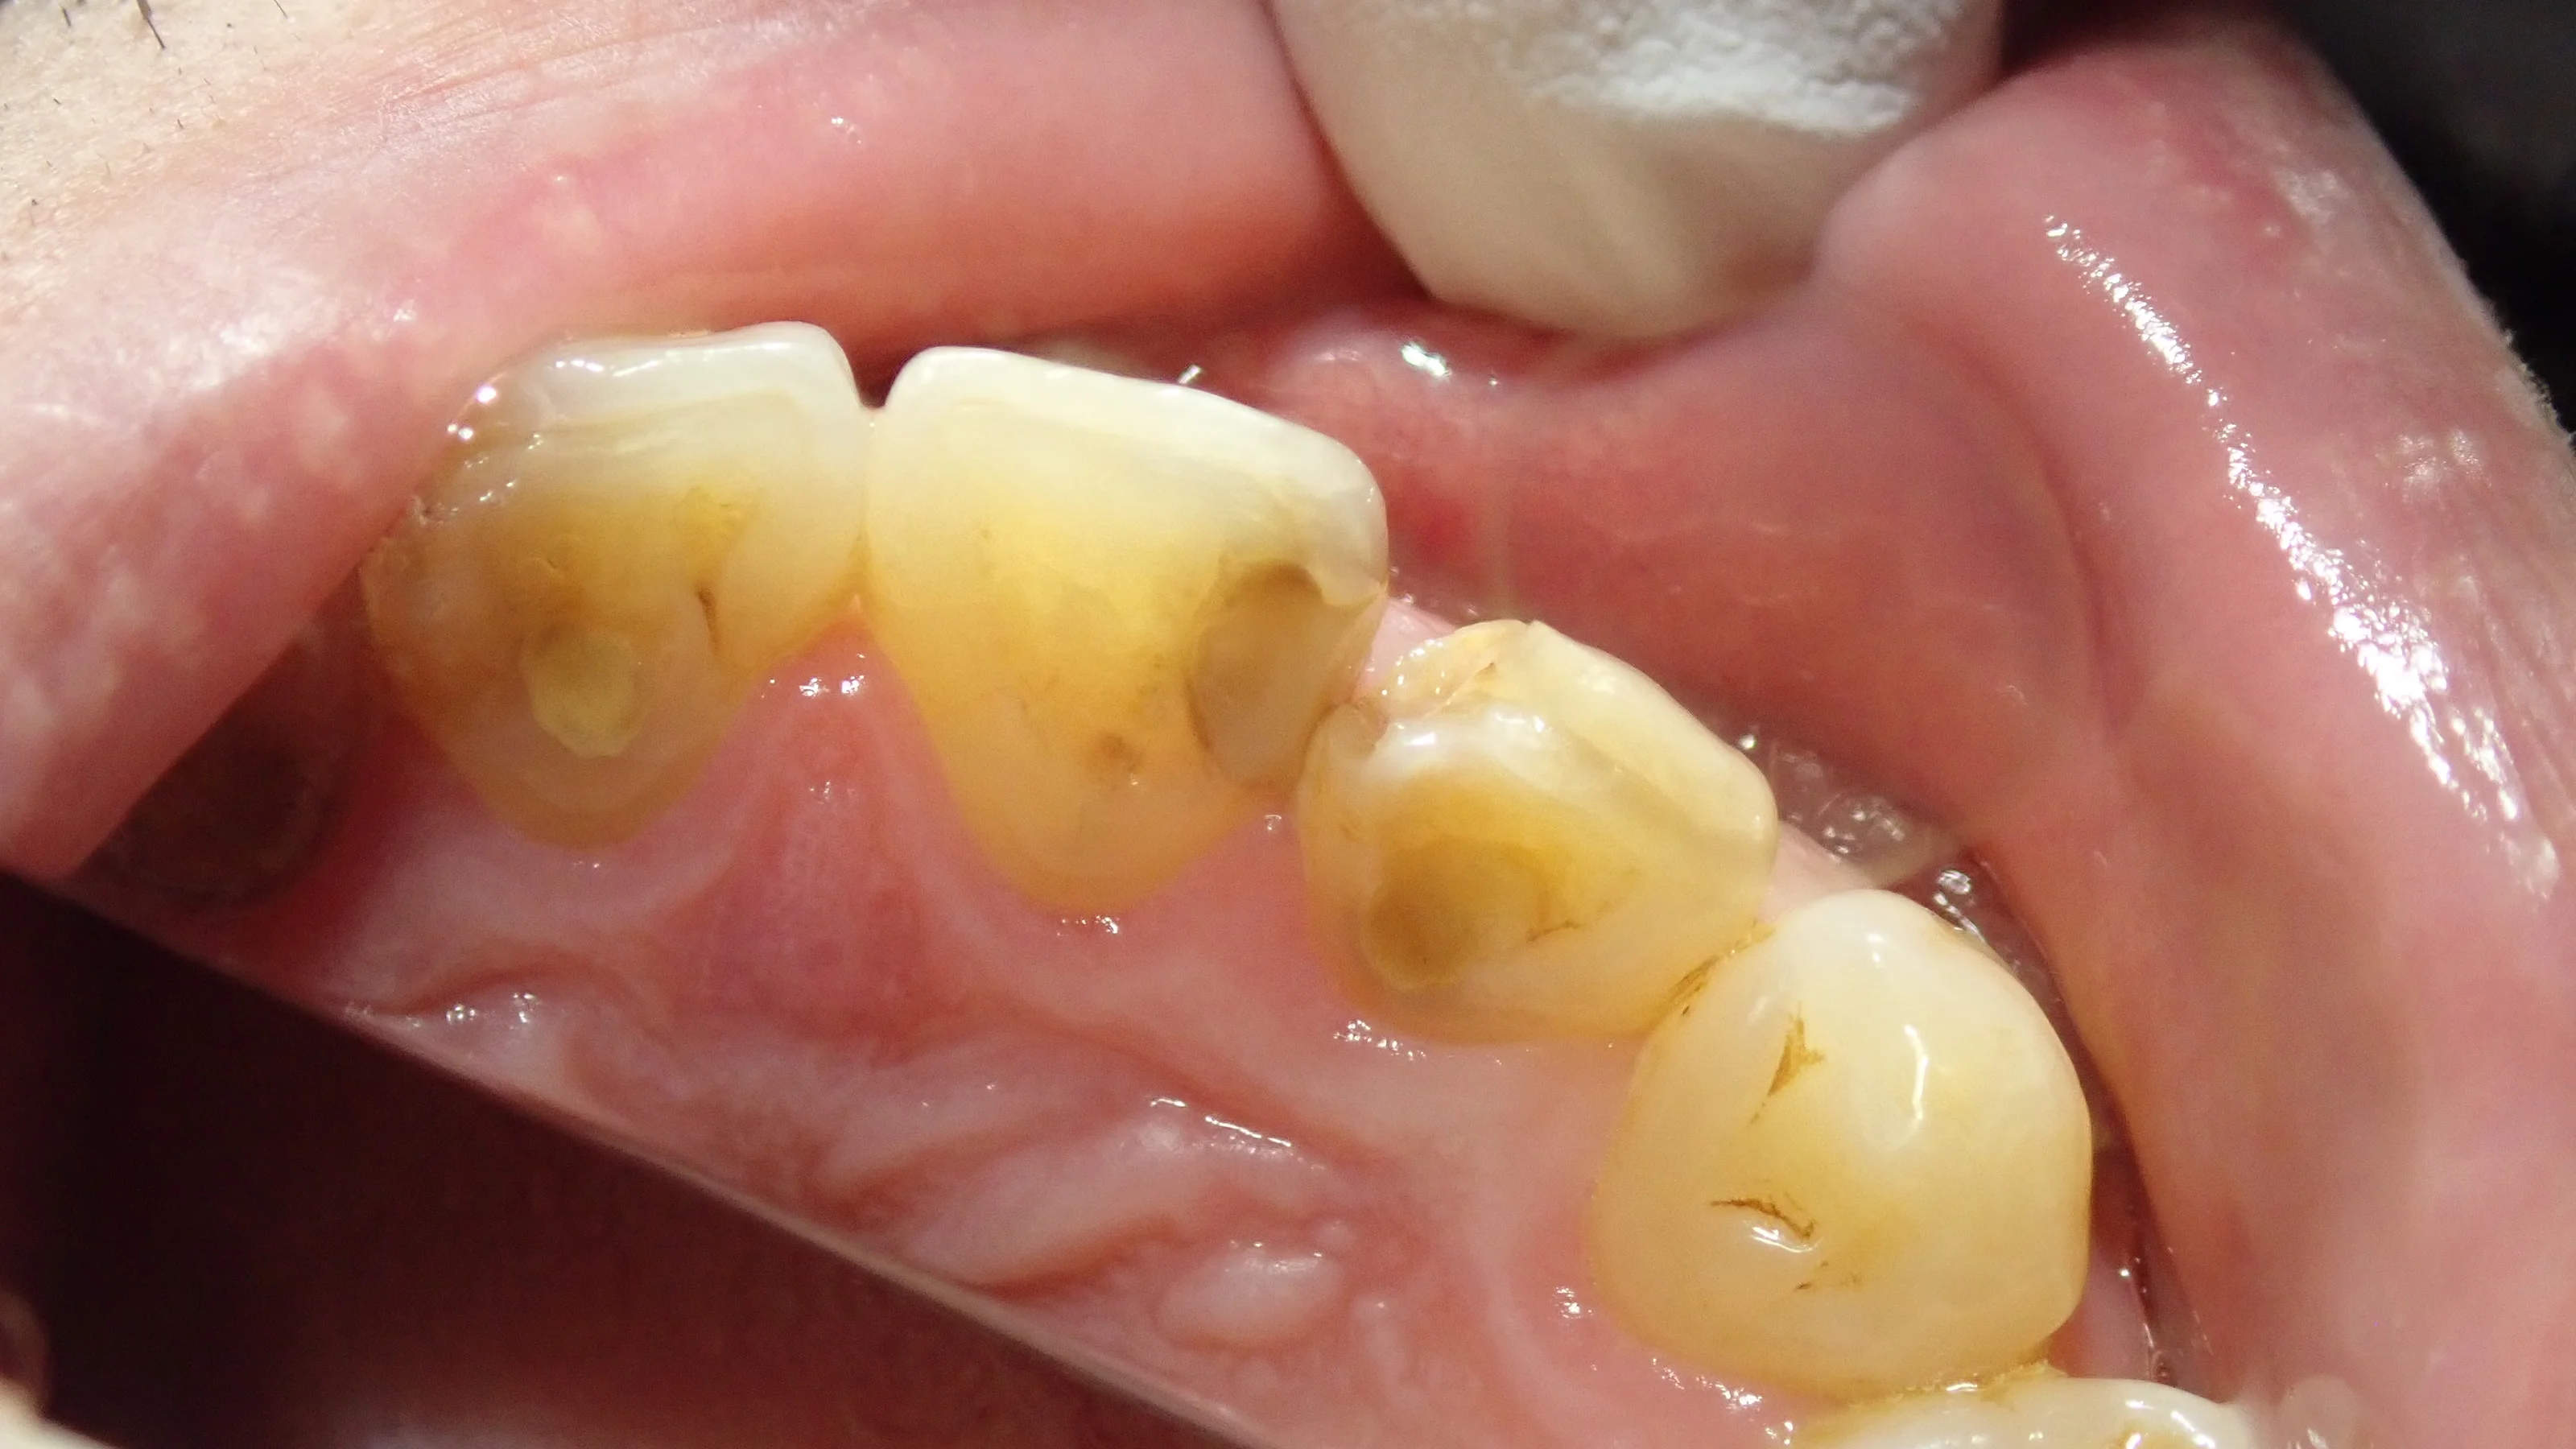

例えば、この方なんですが・・・

前歯の詰め物が割れたって言って来られたんですが、実際は割れたのではなく、虫歯で外れたって感じでした。